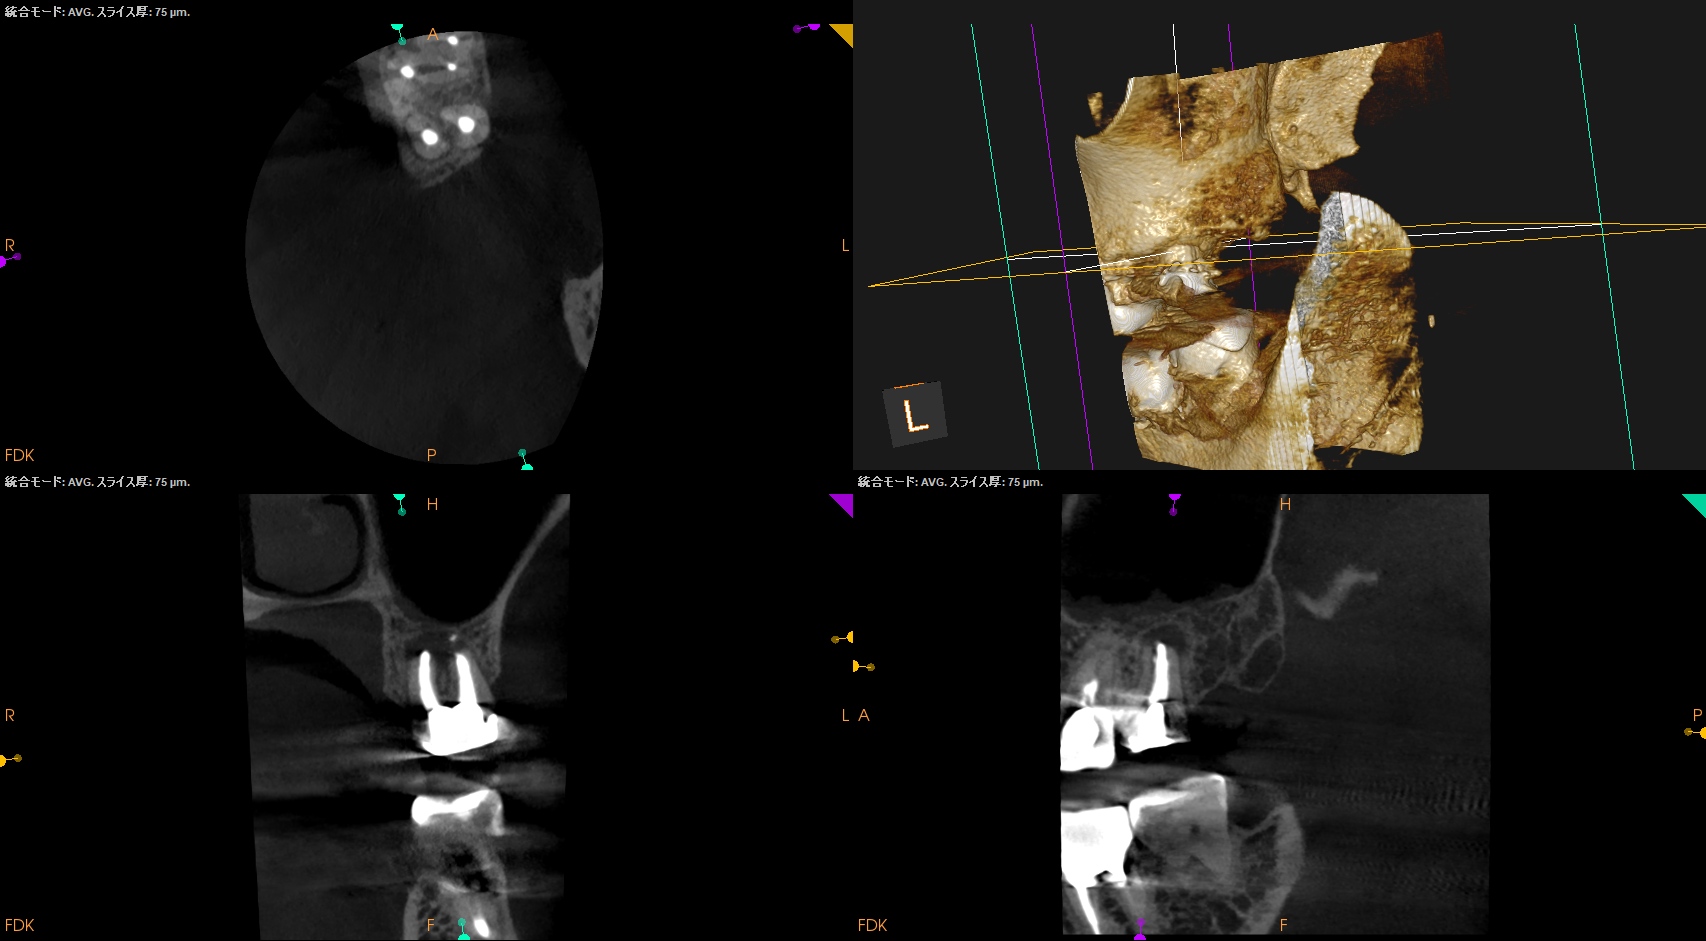

術後にPA, CBCTを撮影した。

この1ヶ月後に再診があり、歯牙をチェックした。

#15 Intentional Replantation 1M recall(2026.1.21)

動揺も生理的な範囲内だ。

ということで、プロビジョナルレストレーションの装着を依頼した。